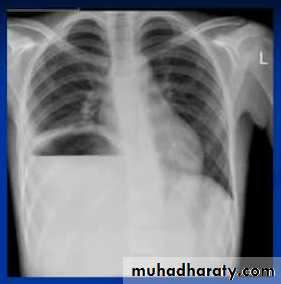

Massive pleural effusion with mediastinal shift to the left.

(A) Chest radiograph(B) CT coronal reconstruction. A massive effusion displaces the mediastinum to the left. CT shows the important pleural effusion together with the enhanced atelectatic left lung.

Note also the depression of the right hemidiaphragm (arrows).